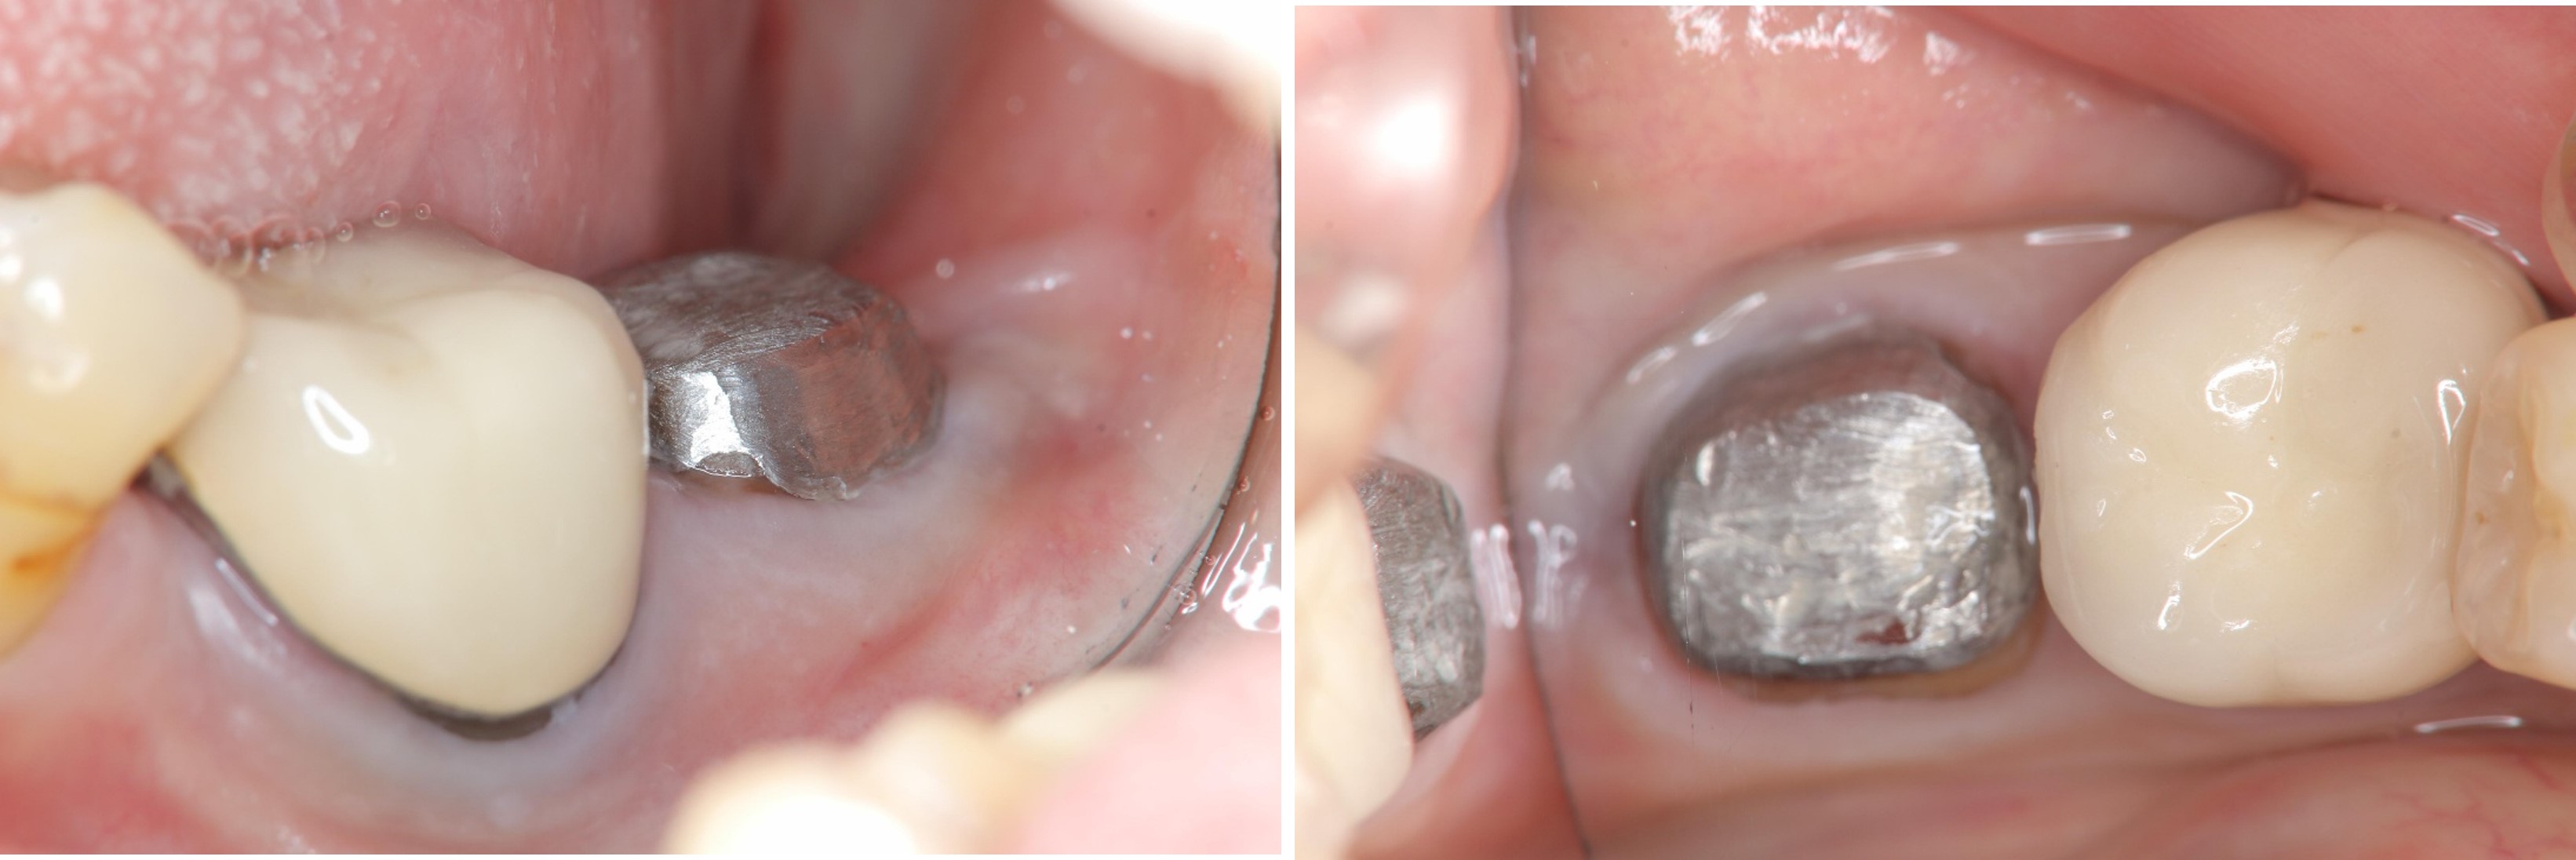

治療前,左下第二大臼齒假牙常脫落,前來求診

之前已根管治療

牙冠增長手術